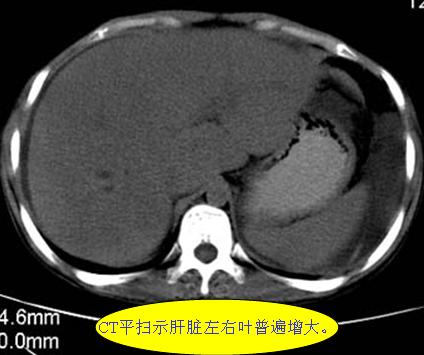

腹部ct解剖与基本病变